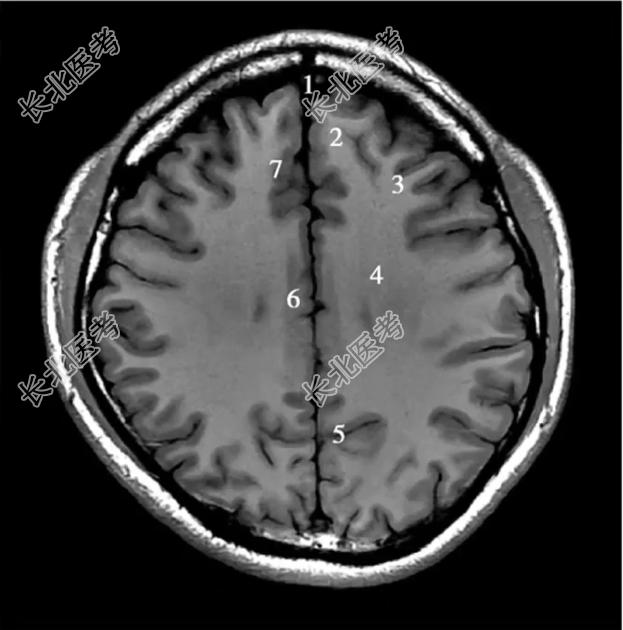

- 单项选择题经半卵圆中心的横断层T1WI中,标记为4的结构是

A、额中回

B、半卵圆中心

C、扣带回

D、额内侧回

E、顶枕沟